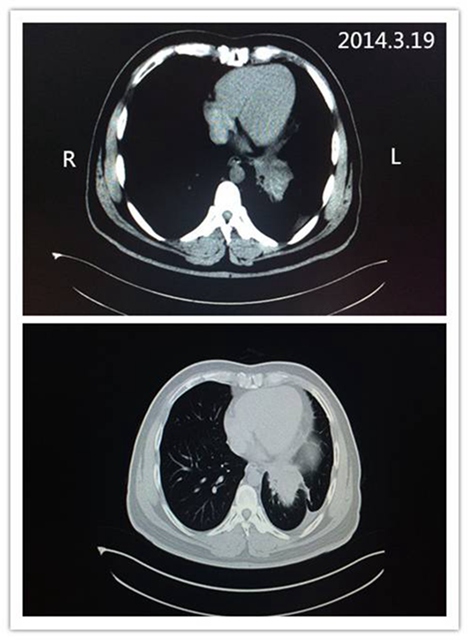

入院后检查,提示胸水增多,病情进展。201312月至20141月行二线化疗,用培美曲塞为基础的方案治疗 2周期 ,症状缓解不明显。仍胸闷气短,右侧肩背部疼痛,需服止痛药方可入睡。行肿瘤组织基因检测结果提示EGFR基因野生型,对TKIs用药不敏感,但ALK基因发生断裂,FISH结果阳性,遂于2014.2.20开始靶向治疗, 用药克唑替尼250mg bid,用药期间无明显药物不良反应。 1月后胸闷、咳嗽、背痛症状消失,停服止痛药。此后,患者定期来素股 定期复查并治疗,现已用药2年余,可以开车外出,正常生活。

服用靶向药后(2016.2.6)CT影像